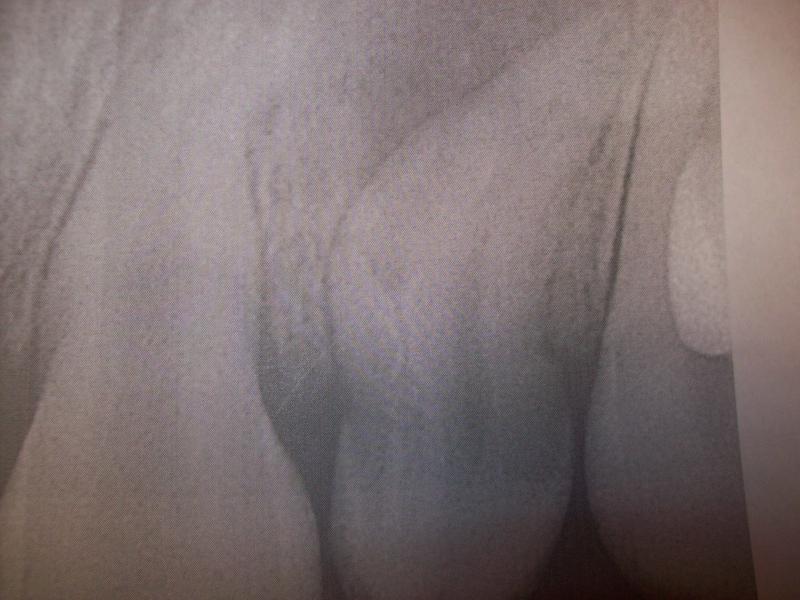

General Dentist,  Performs Root Canals ONLY - Microscope Trained Dentist

"DR. JET'S MISSION IS TO PERFORM  ROOT CANALS FOR A REDUCED FEE USING THE LATEST TECHNOLOGY  AND TECHNIQUES TO SERVICE THE MANY PEOPLE WHO ARE UNINSURED OR UNDER-INSURED GIVING EVERYONE AN OPPORTUNITY TO SAVE THEIR TOOTH!"